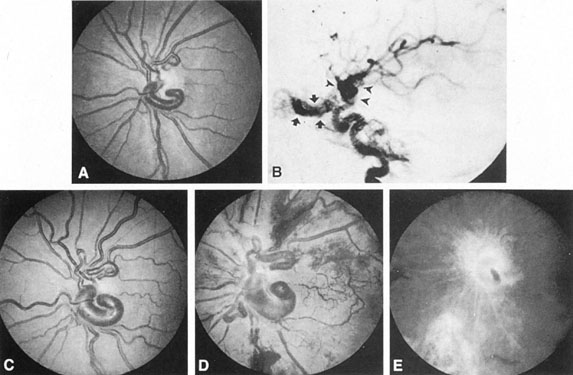

Fig. 7. Supratentorial arteriovenous malformation in a 28-year-old woman with a history of focal motor seizures for many years and a recent subarachnoid hemorrhage. A: Lateral projection carotid arteriogram demonstrating a huge deep hemispheral arteriovenous malformation. B: Frontal projection. C: Fundus photograph showing anomalous tortuous vasculature in each eye. No retinal arteriovenous shunt was detectable.

In general, when hemorrhage occurs involving a portion of the visual radiations, a homonymous visual field defect is to be expected. Selective involvement of the anterior visual pathways may occur either with extensive venous angiomas at the base of the brain or as part of the Wyburn-Mason syndrome (see later), with direct involvement of the optic nerve, chiasm, or tract. Other variants such as congenital cavernous hemangiomas may involve the anterior visual pathways,68 as may intraparenchymal cryptic AVMs69 and present as symptomatic visual loss also resulting from hemorrhage and hematoma. Amaurosis fugax may even be the presenting symptom of supratentorial AVMs when blood is shunted to the meningeal circulation from the ophthalmic artery.70 When supratentorial AVMs drain into dural venous sinuses or the vein of Galen, distant ocular effects evolve, such as proptosis71 or ophthalmoplegia72 because of arterialization of cavernous sinus complex.

Of particular interest are those AVMs that involve the occipital lobe (Fig. 9). The clinical differentiation of migraine from a cerebral AVM was previously regarded as difficult because the clinical features of occipital lobe AVMs include visual phenomena or headaches. However, in most cases the clinical distinction is possible. In 26 cases with occipital AVM, two distinct syndromes were defined in 18 patients: occipital epilepsy and occipital apoplexy.73 Focal seizures with occipital malformations consist of elementary visual sensations similar to the phenomena evoked by direct cortical stimulations. When seizure activity occurs in the striate cortex (area 17), the patient usually reports sensations of moving lights in the right or left homonymous fields. The sensations are poorly formed, episodic, usually brief, sometimes colored, and unassociated with the angular, scintillating figures so characteristic of migrainous cortical phenomena. Epileptic discharges from areas 18 and 19 cause photopsias that are unlikely to remain stationary and to flicker rapidly. The epileptic photopsias usually last only seconds; occasionally they last for a few minutes before the onset of a generalized seizure. In other instances only the brief visual episodes occur without spreading to produce a generalized seizure. Momentary dimming or blindness in one or both homonymous fields may be experienced with seizure activity in the occipital areas.

Fig. 9. Carotid arteriogram of an occipital lobe arteriovenous malformation (AVM). Lateral (A) and frontal (B) projections demonstrating a small occipital AVM (arrow). The patient was a 23-year-old woman who presented with severe apoplectic unilateral headache, total left homonymous hemianopia, and mild nuchal rigidity. Despite xanthochromic cerebrospinal fluid, she was initially diagnosed elsewhere as having migraine. An AVM was successfully resected, and a small occipital lobe hematoma was removed.